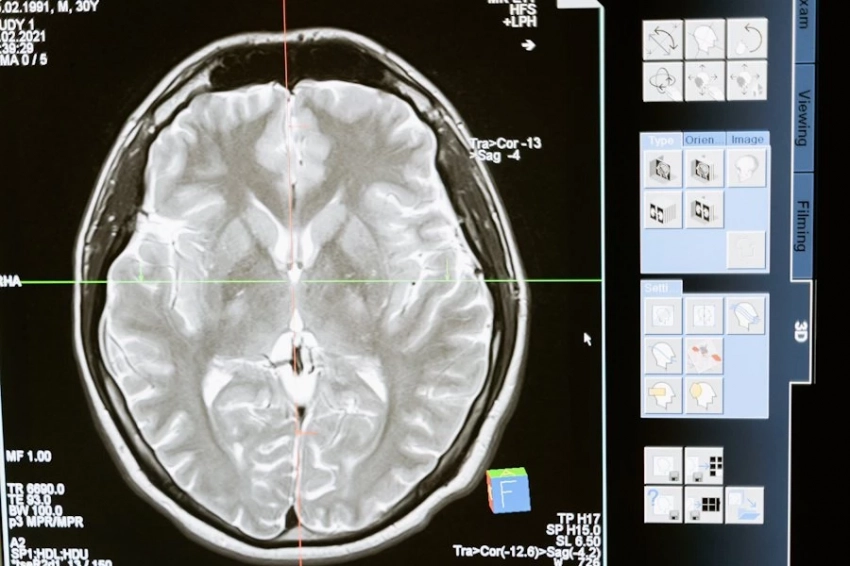

Учеными Университетского колледжа Лондона выяснено, что гормон голода грелин, вырабатываясь в кишечнике, способен влиять на мозг, на принятие решений, связанных с пищевым поведением.

Как сообщает журнал Neuron, грелин, активизируя гиппокамп, может стать инструментом подавления излишнего аппетита. Открытие помогло лучше проанализировать механизмы регуляции пищевого поведения и глубже выявить связь между пищей и другими факторами здоровья.

Исследователи выпустили мышей на арену, где было немного еды. Наблюдали за их поведением и отслеживали нейронную активность мозга. Все грызуны исследовали пищу, но есть принимались лишь голодные животные. Ученые изучили активность мозга в вентральной (нижней) части гиппокампа, отвечающей за принятие решений, формирующей и использующей воспоминания для управления поведением.

Активность в вентральной части гиппокампа увеличивалась, когда мыши приближались к еде, что мешало животному есть. Но когда мышь была голодна, нейронная активность данной зоны уменьшалась, и гиппокамп больше не мешал принимать пищу. Это состояние соответствует повышенному уровню циркуляции в крови гормона голода грелина.